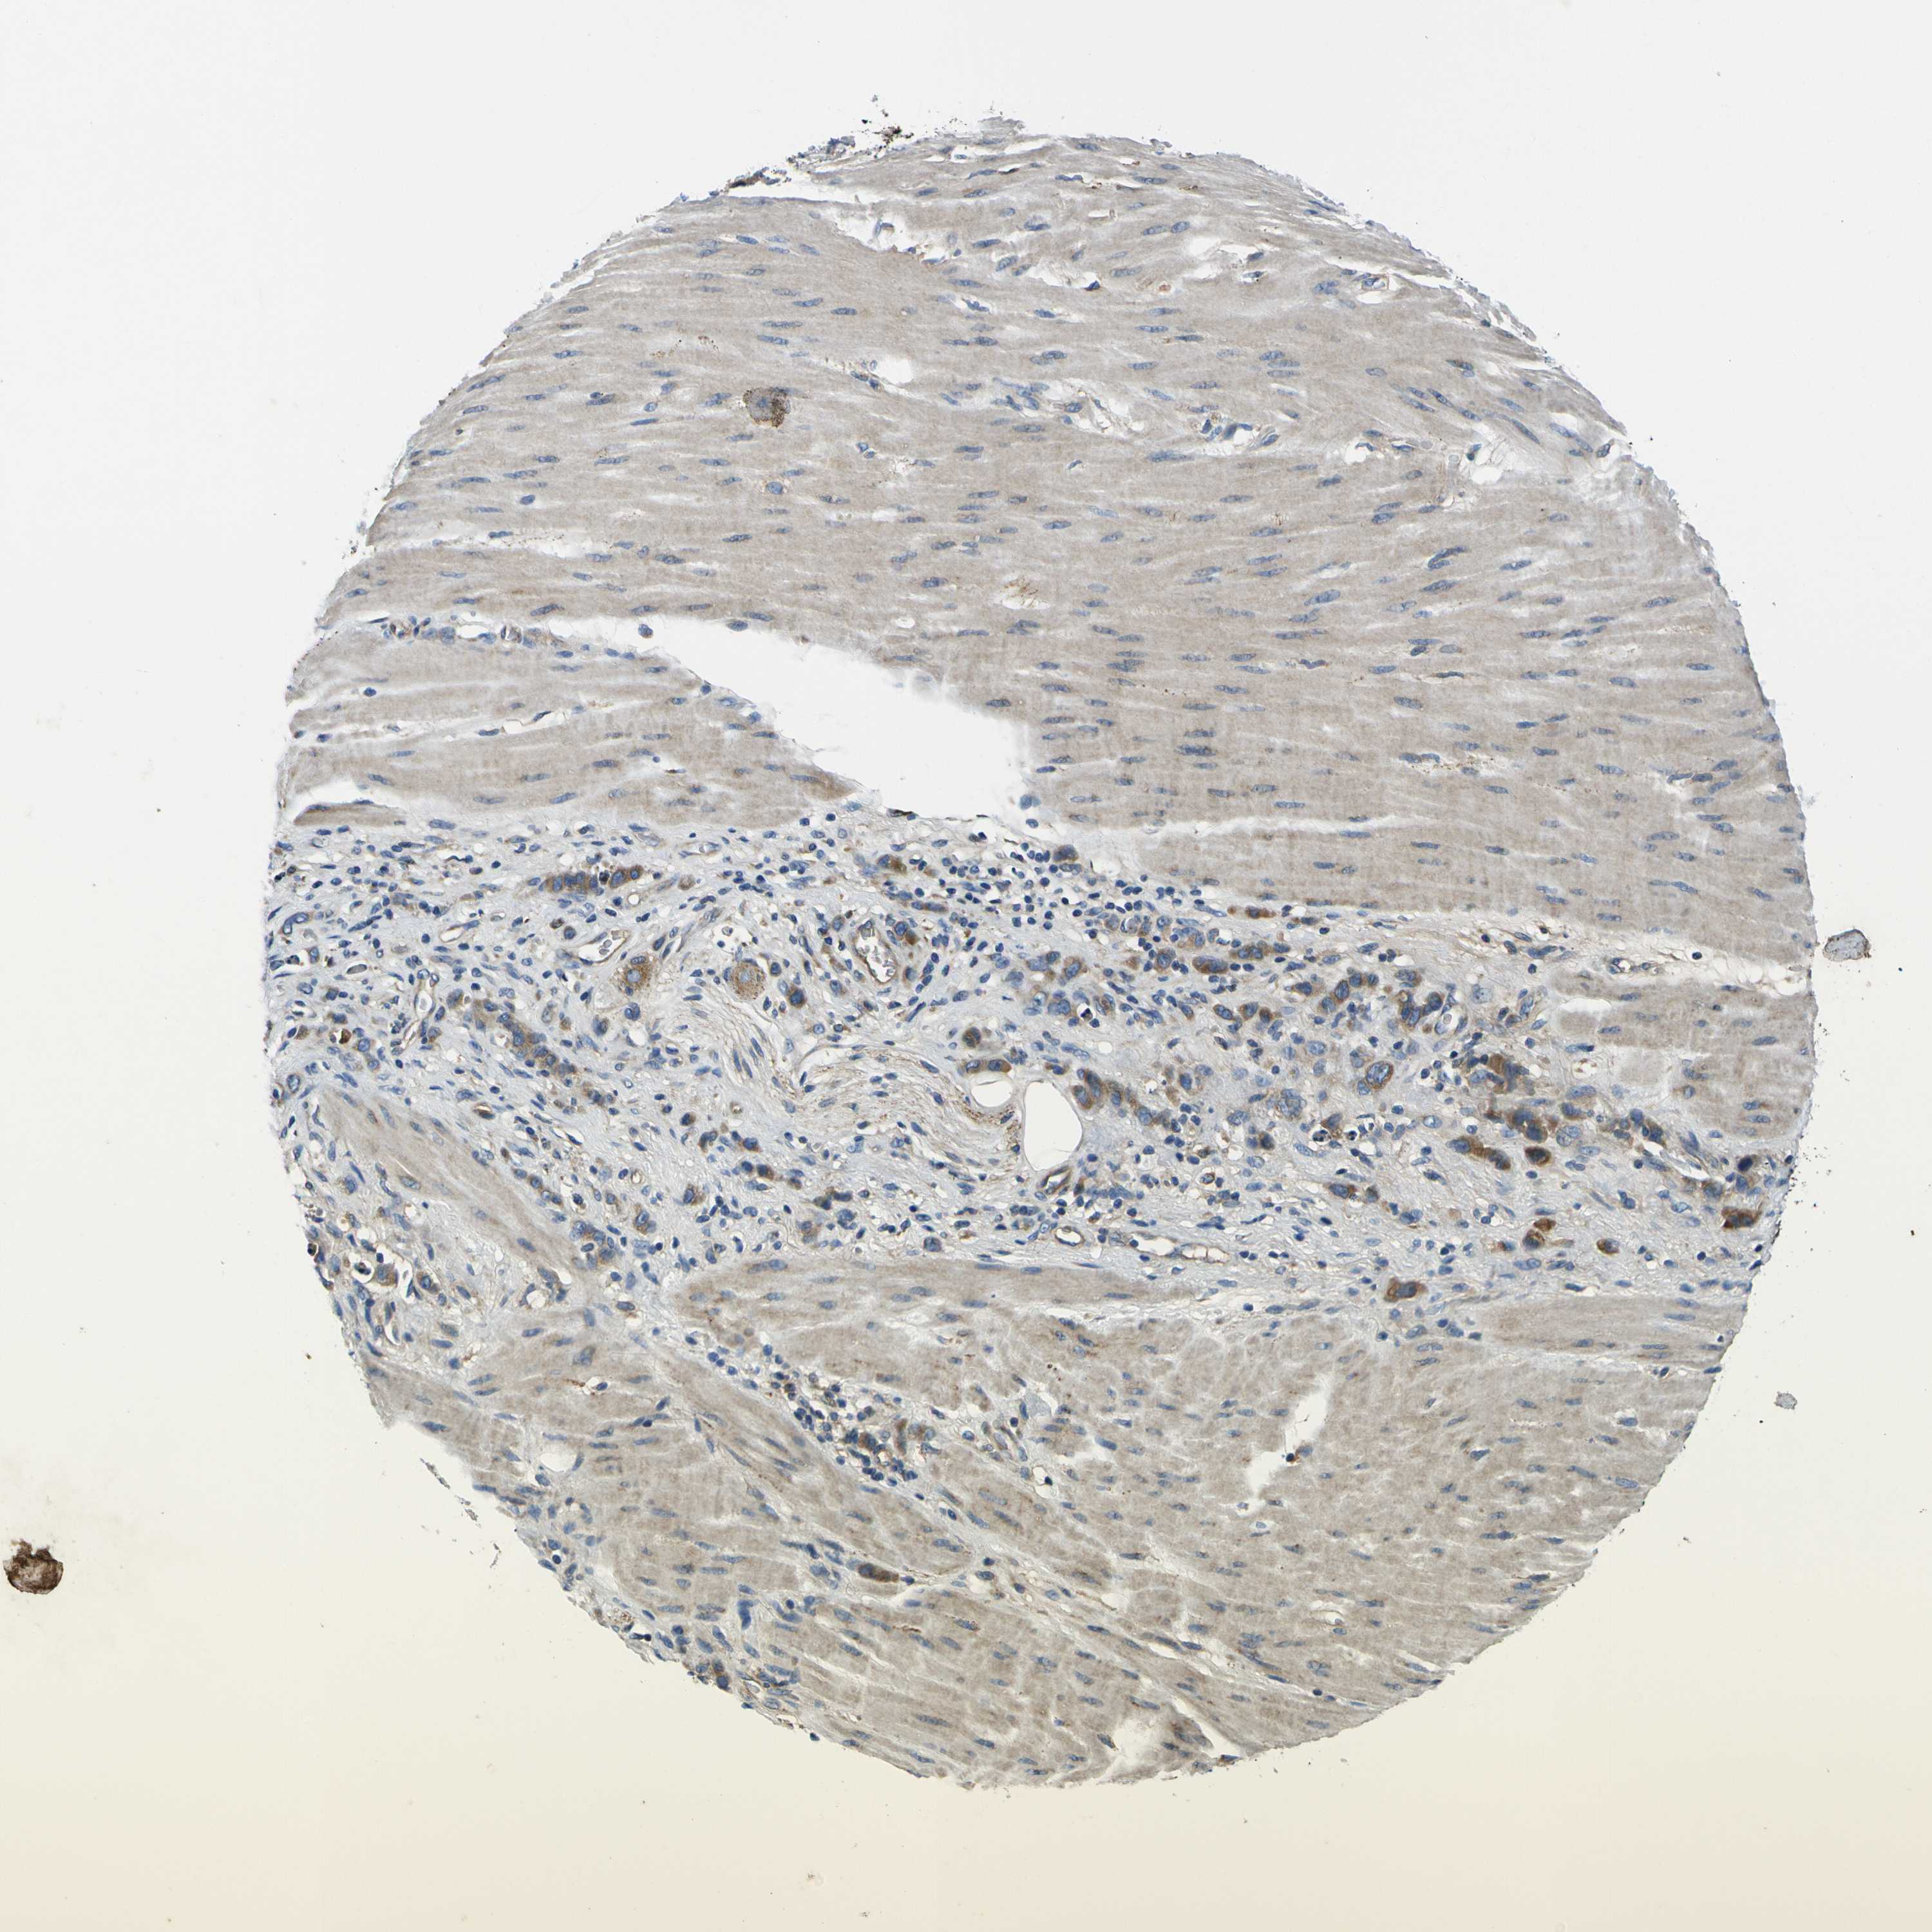

STOMACH CANCER - Protein expressioni

A mouse-over function shows sample information and annotation data. Click on an image to view it in a full screen mode. Samples can be filtered based on level of antibody staining by selecting one or several of the following categories: high, medium, low and not detected. The assay and annotation is described here.

Antibody stainingi

Antibody staining in the annotated cell types in the current human tissue is reported as not detected, low, medium, or high, based on conventional immunohistochemistry profiling in selected tissues. This score is based on the combination of the staining intensity and fraction of stained cells.

Each image is clickable and will lead to virtual microscopy that enables deeper exploration of all samples and also displays staining intensity scores, fraction scores and subcellular localization as well as patient and tissue information for each sample.

Antibody HPA056141

Antibody CAB010225

Staining

High

Medium

Low

Not detected

Intensity

Strong

Moderate

Weak

Negative

Quantity

>75%

75%-25%

<25%

None

Location

Nuclear

Cytoplasmic/membranous

Cytoplasmic/membranous,nuclear

Adenocarcinoma, NOS

Adenocarcinoma, High grade